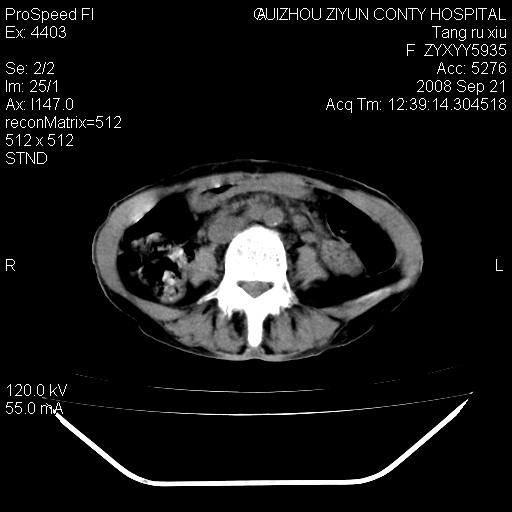

f、57岁,上腹痛.2月,近来胸闷。2月前在外院摄胸片示左侧胸腔少量积液。

(患者腹痛入院,欲吐,临床医生说禁饮,所以没有口服对比剂)

肝脏大小形态尚可,其实质内可见多发大小不等的低密度影,边缘模糊。肝门区结构紊乱,腔静脉腹主动脉旁可见多发软组织密度影,部分融合成团块状,并向下延伸。胰腺及十二指肠结构显示不清。腹腔内脐后肠管走形僵硬,管壁可见增厚。盆腔内可见多个淋巴结影。所扫层面左侧胸腔可见大量弧形水样密度影,其内侧可见被压缩的肺组织影。左侧胸壁可见一小结节样软组织密度影,边缘模糊。心脏纵隔向右侧移位。心脏包膜内可见囊样低密度影,其内侧心房室周围可见一圈气体样密度影。纵隔内大血管旁可见多发软组织团块影,部分融合。

1.腹膜后淋巴瘤侵及肝脏,肺内及纵隔内多发转移。2.左侧大量胸腔积液并压缩性肺不张。3.心包脓肿可能,转移不除外。4.脐后局部肠管管壁增厚,考虑炎症可能,肿瘤不除外。

为什么没有人注意到腹腔脐后的那段肠管呢?那段看着很不好的样子。